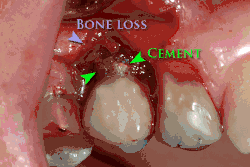

Установка зубных имплантатов может вести к периимплантиту, который возникает из-за бактериальной флоры, попадающей на внешнюю поверхность имплантатов через зубной налет. Лечение данного заболевания проводили корейские исследователи с использованием титановой щетки.